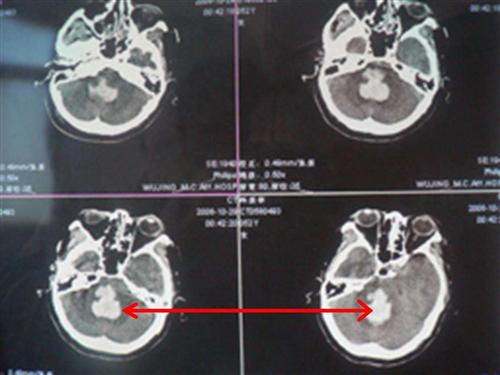

相关图片